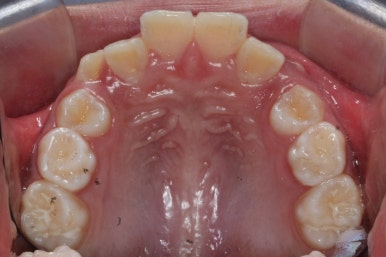

골격분석과 X-ray 등으로 확인했을 때, 이번 환자분은 위턱이 약간 상대적으로 나와있다고 판단이 되었습니다. 위쪽 치열은 아래쪽 보다 앞으로 나와있으며 특히 어금니가 앞쪽으로 나와있었어요.

따라서 교정계획은 헤드기어를 사용해 위쪽 어금니는 뒤로 밀고 영구치가 추후 맹출이 될 때 까지 시간을 주자는 것이였어요.

최대한 비발치로 연산동덧니교정을 하자는 판단이며 성장기에는 공간만 충분하다면 삐뚤했던 치아도 자리를 어느정도 잡기 때문입니다.

위쪽 어금니를 뒤로 밀어주기 위해 헤드기어라는 장치를 사용했습니다.

아직 유치가 몇 개 남아있기에 장치가 전체적으로 부착되지 않습니다. 우선 앞니 4개만 먼저 치열을 맞추고 위쪽 어금니는 후방 이동을 해주면서 교합을 맞추며 덧니가 내려올 공간을 확보합니다.